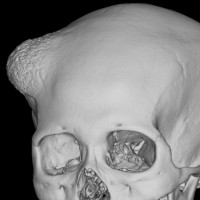

骨内髄膜腫 osseous meningioma

骨内増殖をする髄膜腫です。頭蓋骨腫瘍と間違えるようなものです。触った感じは骨腫ですが,CTでは,表面が毛羽立っていて,頭蓋冠に浸潤していることが特徴です。浅側頭動脈からの豊富な血流があります。

わずかですが頭蓋内にも腫瘍があり,硬膜が肥厚してガドリニウム増強されます。

頭蓋骨をかなり広範におかすので骨は捨てません。開頭して取り外した骨の厚くなっている部分と髄膜腫で軟らかくなっている部分を削除して,それから骨片をオートクレーブで短時間熱処理して,元あった所にもどします。下の画像は手術後1年半が経過したものですが,髄膜腫の再発はなく,熱処理骨弁は吸収されないで生着しています。